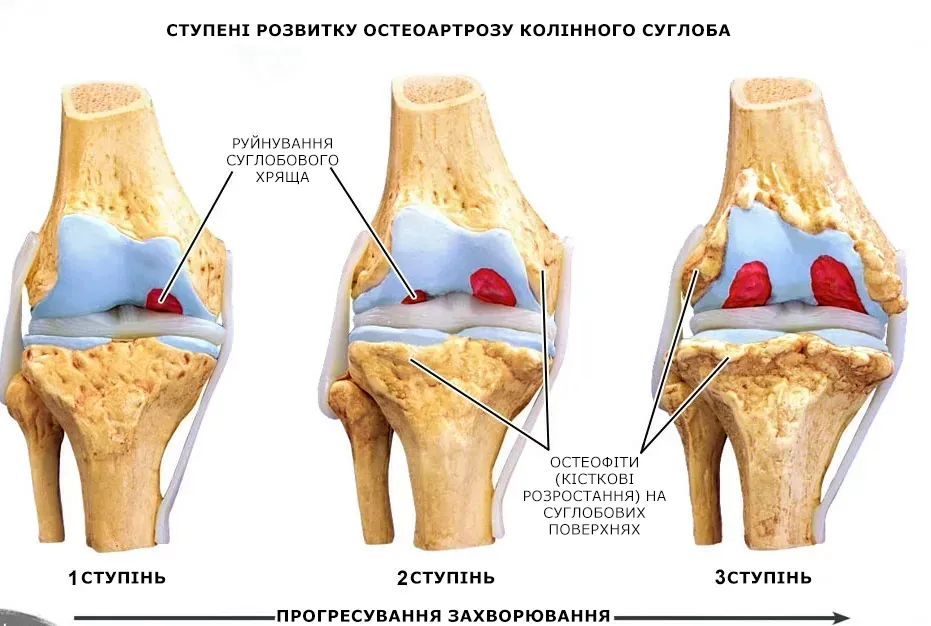

Поїхала в районну лікарню до Львова, там мені зробили недешеве обстеження. Через кілька годин результати були готові, і мій лікар сказав: “Чому ви ігнорували симптоми раніше? У вас артроз! Ви його запустили до 2 стадії. Якщо хочете не стати інвалідом, вам потрібно робити операцію на стегні та колінах!”

ЗАПАМ'ЯТАЙТЕ: АРТРИТ І АРТРОЗ РУЙНУЮТЬ ХРЯЩОВУ ТКАНИНУ ЗА 3 РОКИ! Пігулки та мазі від артрозу, навряд чи вам допоможуть, вам потрібна операція…

Мені довелося придбати інвалідний візок і в ньому пересуватися по дому. Лікар казав, що за 3 роки артроз руйнує хрящову тканину, але у мене, мабуть, він почався набагато раніше. Спочатку я майже не відчувала, що у мене хворі суглоби, а потім, все так різко загострилося, і я непомітно опинилася в інвалідному візку, без надії на одужання. Як згадаю,